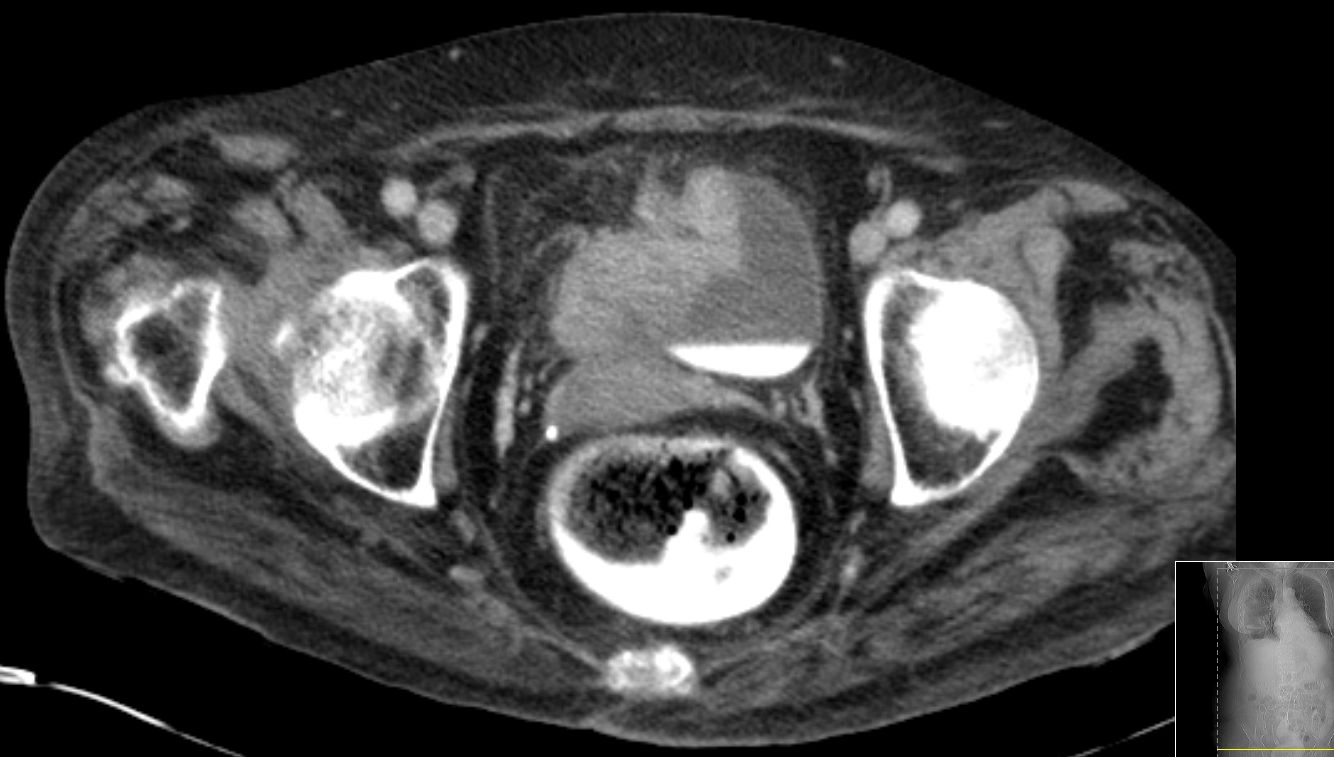

| T4-Tumor | 67-jährige demente Frau mit T4-Blasentumor

(invasives Urothelkarzinom) und Rektumkarzinom.![]()  |